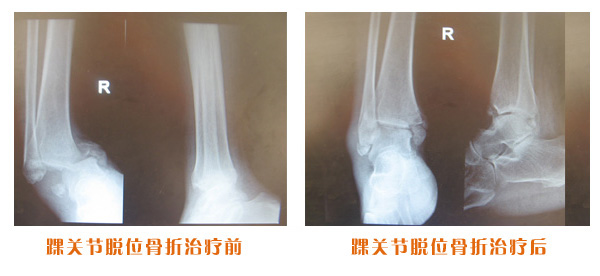

踝關(guān)節(jié)脫位骨折治療前后對比